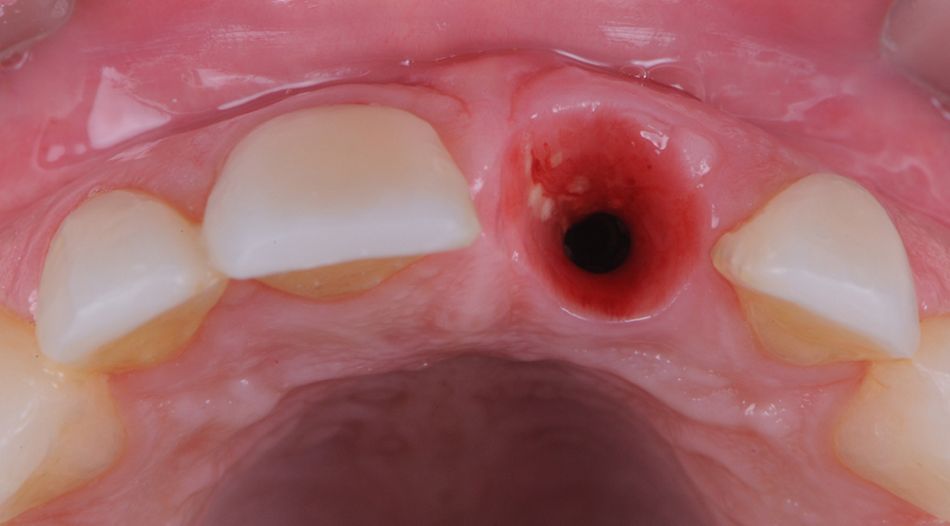

After six weeks of healing with no postoperative complications and stable osseointegration, the healing abutment was removed, the site irrigated with 0.12% chlorhexidine gluconate, and satisfactory healing was verified (Figs. 28-31).